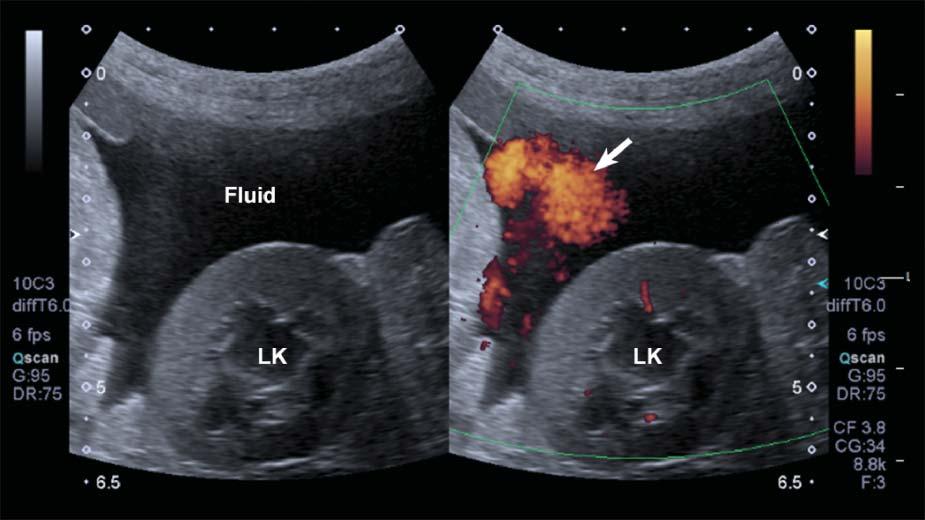

DopplerFlashArtifact

Rapidmovementofthepatient’sbody,ofastructural component(e.g.,heartorarterialpulsation),orofthe probemightleadtoDopplershiftsbeinginterpreted bythesystemasbloodflow.Aspuriousappearance

ofbloodflowisdisplayed,limitingtheassessmentof truevessels.Thisartifacttendstobemoreapparentin fluid-filledstructuresandwithascites(Figure1.25).

Figure1.25. Flash. SpuriousechoesoftenappearwhenusingpowerDopplerinmovingpatientsorwhenascitesispresent, limitingtheassessmentthetissueperfusioninthesecases.LK,leftkidney.